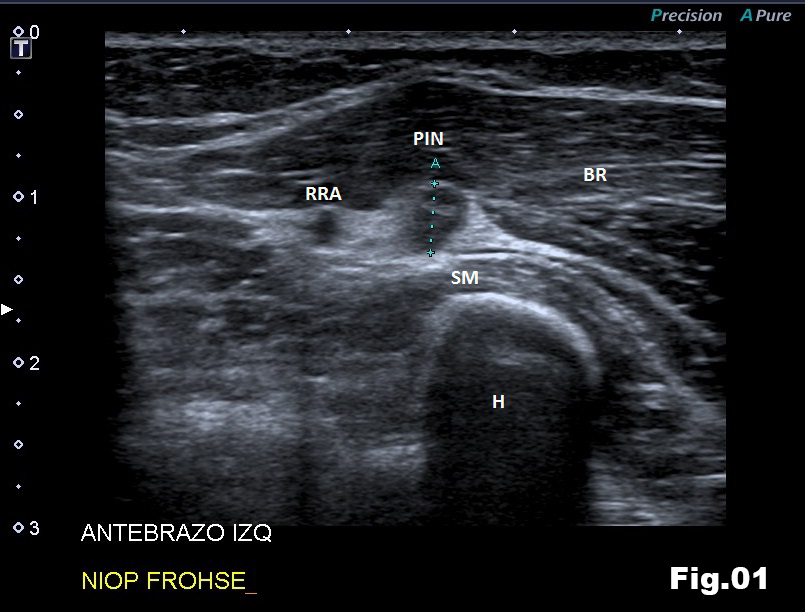

A 51-years-old healthy female, with no history of upper limb injuries, complained of an anterior and proximal left forearm tenderness associated with weakness of the extensor muscles of the forearm. An ultrasound scan was performed and demonstrated a thickened and hypoechoic posterior interosseous nerve (PIN) at the arcade of Frohse, with hypervascularization of the perineurium. In its deeper aspect, there was a subtle irregularity of the radial metaphysis (Fig1,2). The plain film showed a sessile irregularity of the anterior region of the metaphysis (Fig 3). Unenhanced MRI and CT scan were also performed. The CT scan showed the irregularity of the radius (Fig 4) and in the MRI (Fig 5), it was reported as an osteochondroma like metaphyseal lesion of the radius. Initial treatment included a corticosteroid injection around the PIN, but without decrease of symptomatology. The orthopedic surgeon then proceeded with an osteochondroma resection to release the PIN. The upper limb surgical team performed the surgery (Fig 6), and they found a thickened, hyperaemic PIN, adjacent to the osteochondroma (Fig 6,7). They resected the osteochondroma and debrided the PIN (Fig 8). The patient recovered full muscular strength and the tenderness progressively disappeared.

This case report illustrates that evaluation of the PIN, Arcade of Frohse, and radial recurrent artery are very dificult with standard elbow MRI, because small structures (diameters below 5 mm) are beyond the resolution of MRI typically using fields of view (FOV) of 12,0 x 18,6 cm and slice thickness of 3 mm.

With these parameters, obtaining a well defined image of a small structure is almost impossible. However, high frequency ultrasound scans allow high resolution imaging and assessment of these small structures. Furthermore, Power and color Doppler is also a useful adjunct to evaluate the perineural vascularisation.

Fig 2: Ultrasound long axis view of the AF (Arcade of Frohse), showing a swelled PIN and its anatomical relationship with the radius osteochondroma (arrow). SM (Supinator Muscle), BR (Brachioradialis muscle) and R (Radius metaphysis).